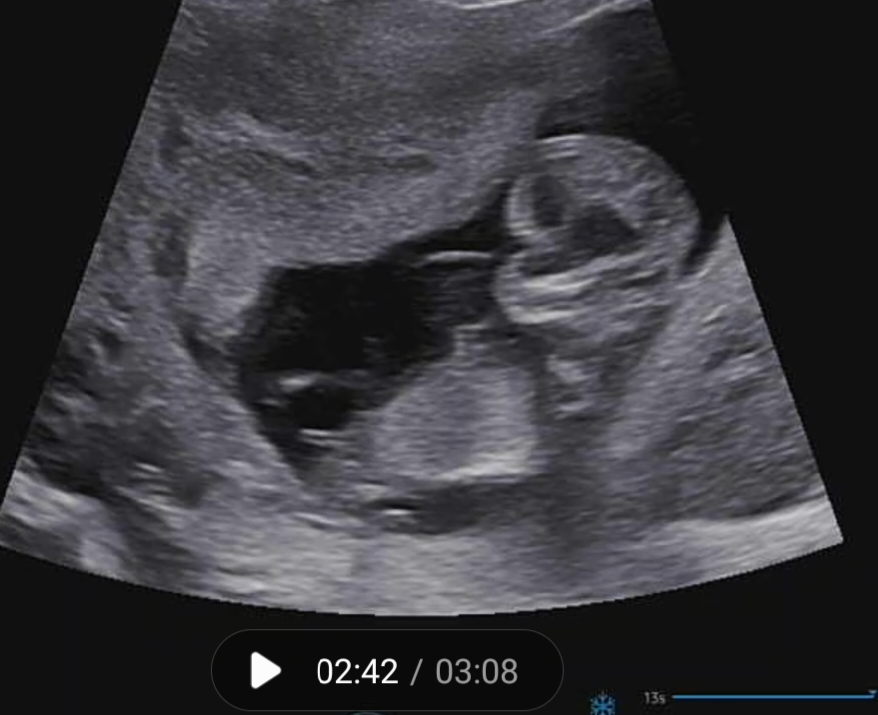

12주2일에본 초은파사진..🌶일까요 🍑일까용??

너무궁금해요ㅜㅜ 댓글부탁드릴게요옹...뭐같아보이세용>? 저부분이...🌶일까요??ㅋㅋㅋㅋ